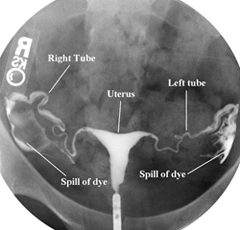

나팔관 조영술은 말 그대로 자궁을 통해 나팔관에 조영제를 흘려넣는 시술로, 자궁에서 난소로 이어진 관이 잘 뚫려 있는지 확인하고자 하는 목적이다. 조영제를 정액이라 치면, 이 시술을 통해 정액이 난소까지 무리없이 도착할 수 있는지를 확인해볼 수 있으니 자궁내 정액 이동 시뮬레이션(?)이라고도 할 수 있으려나. 간혹 중간에 유착이 있거나해서 막힌 부분이 있다면 정자와 난자가 만날 수조차 없을테니 나팔관 조영술은 난임 검사에 필수 항목이다. (그리고 이렇게 한번 뚫어주면 유착이 없었다 하더라도 길이 잘 열려 임신이 잘된다는 썰도 있다. 과연??)

시술 후 진료실로 자리를 옮겼다. 의사 선생님이 나의 나팔관에 조영제가 들어가는 영상을 보여주며 설명해 주시는데, 나팔관이 내가 알던 것과 차이가 있어 좀 놀랐다. 흔히 도식화된 이미지에서 나팔관은 역삼각형의 자궁 양쪽 상단에서 뻗어나와 우아하게 팔로 난소를 감싸안는 모양이었다. 그러나 초음파에 찍힌 내 나팔관은 아무렇게나 흘려 놓은 가느다란 실가닥에 더 가까워 보였다.

실제 나팔관 모습 (출처: https://dallasivf.com)

좁은 부분은 심지어 머리카락 두께밖에 되지 않는다고 한다. 눈에 보이지도 않는 작은 세포들이 이렇게 꼬부랑거리는 길고 좁은 길을 달려가야 한다는 말인가. 정자난자가 서로 잘 못 만나는게 당연해 보였다. 어찌저찌 수정란이 되어도 데굴데굴 다시 자궁 쪽으로 굴러가면서 세포분열까지 해야 한다는데 이렇게 험한 길이라니. 뻥뚫린 8차선도로여도 모자랄 판에 이렇게 좁고 길고 구불거리다니!